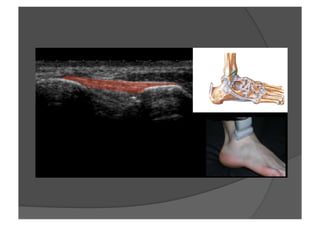

Explorer la zone grisée pré-fibulaire

Elément de la syndesmose tibio-fibulaire inférieure

—  Ligament tibio-fibulaire antéro-inférieur = LTFAI , 1er lésé

Fibula Tibia

LTFAI

LTFA